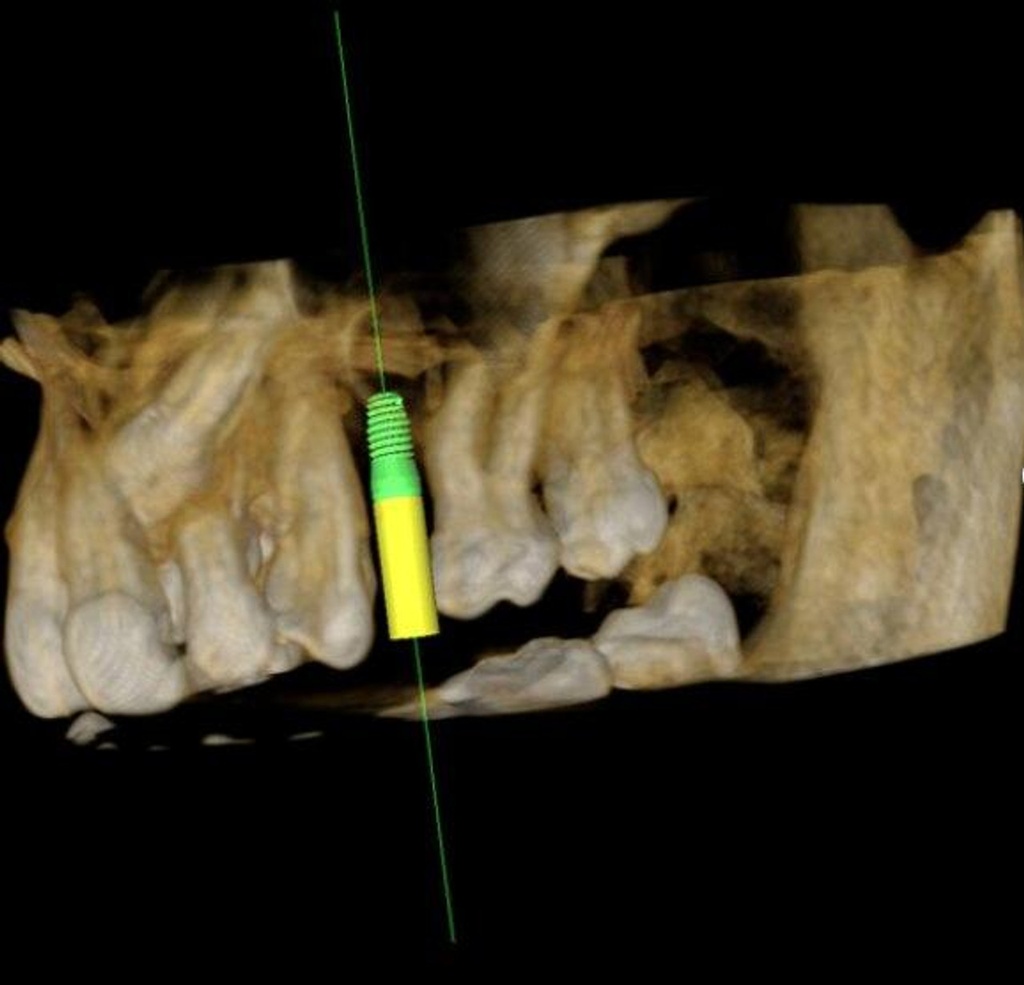

Introducing the CS 9300 Premium Panoramic, Cephalometric, and Cone Beam System from Carestream Dental – your ultimate solution for top-quality dental imaging. This state-of-the-art machine offers both 2D panoramic and cephalometric dental X-rays, as well as adjustable 3D cone beam images in up to seven different field of view sizes, extending up to 17x13.5 cm. This comprehensive range of imaging capabilities makes it a versatile tool, perfect for supporting a wide array of dental, surgical, or orthodontic examinations.

With the CS 9300 Premium, you can expect unparalleled image clarity and precision, allowing you to confidently diagnose and plan treatments with ease. Whether you're performing routine dental check-ups, complex surgical procedures, or orthodontic assessments, this system ensures outstanding results.

- Implantology

3D MODALITY: Large FOV

3D FIELD OF VIEW (IN CM): 5x5, 10x5, 8x8, 10x10, 17x6, 17x11, 17x13.5